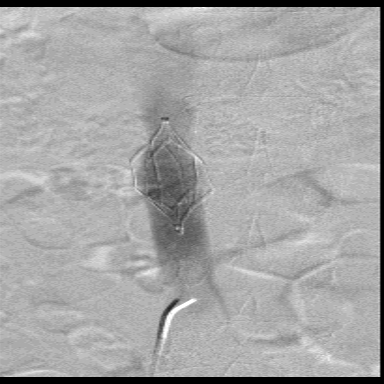

图为:入院后再次尝试腔内回收滤器,经4h努力以失败告终

图为:腹腔镜下腔静脉切开滤器取出